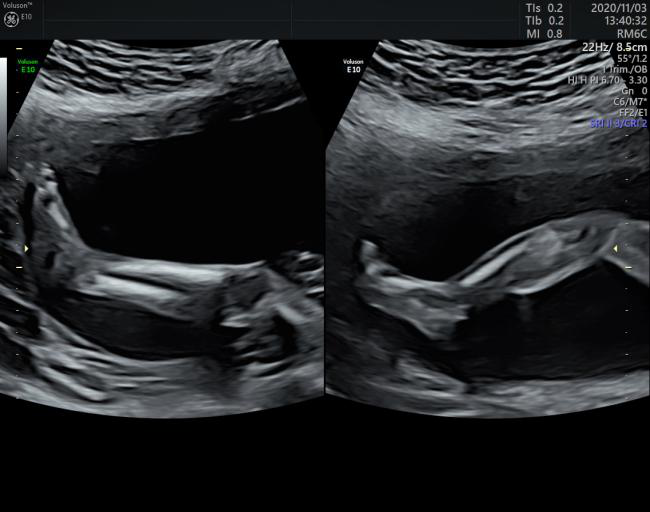

卓越的二维图像图像质量

VOlusonE什么彩超机世界顶级四维彩超机美国 GE Voluson E10 BT20金标版落户吉林省吉林中西医结合医院_https://www.jmylbn.com_新闻资讯_第4张

VOlusonE什么彩超机世界顶级四维彩超机美国 GE Voluson E10 BT20金标版落户吉林省吉林中西医结合医院_https://www.jmylbn.com_新闻资讯_第5张

胎儿的耳朵